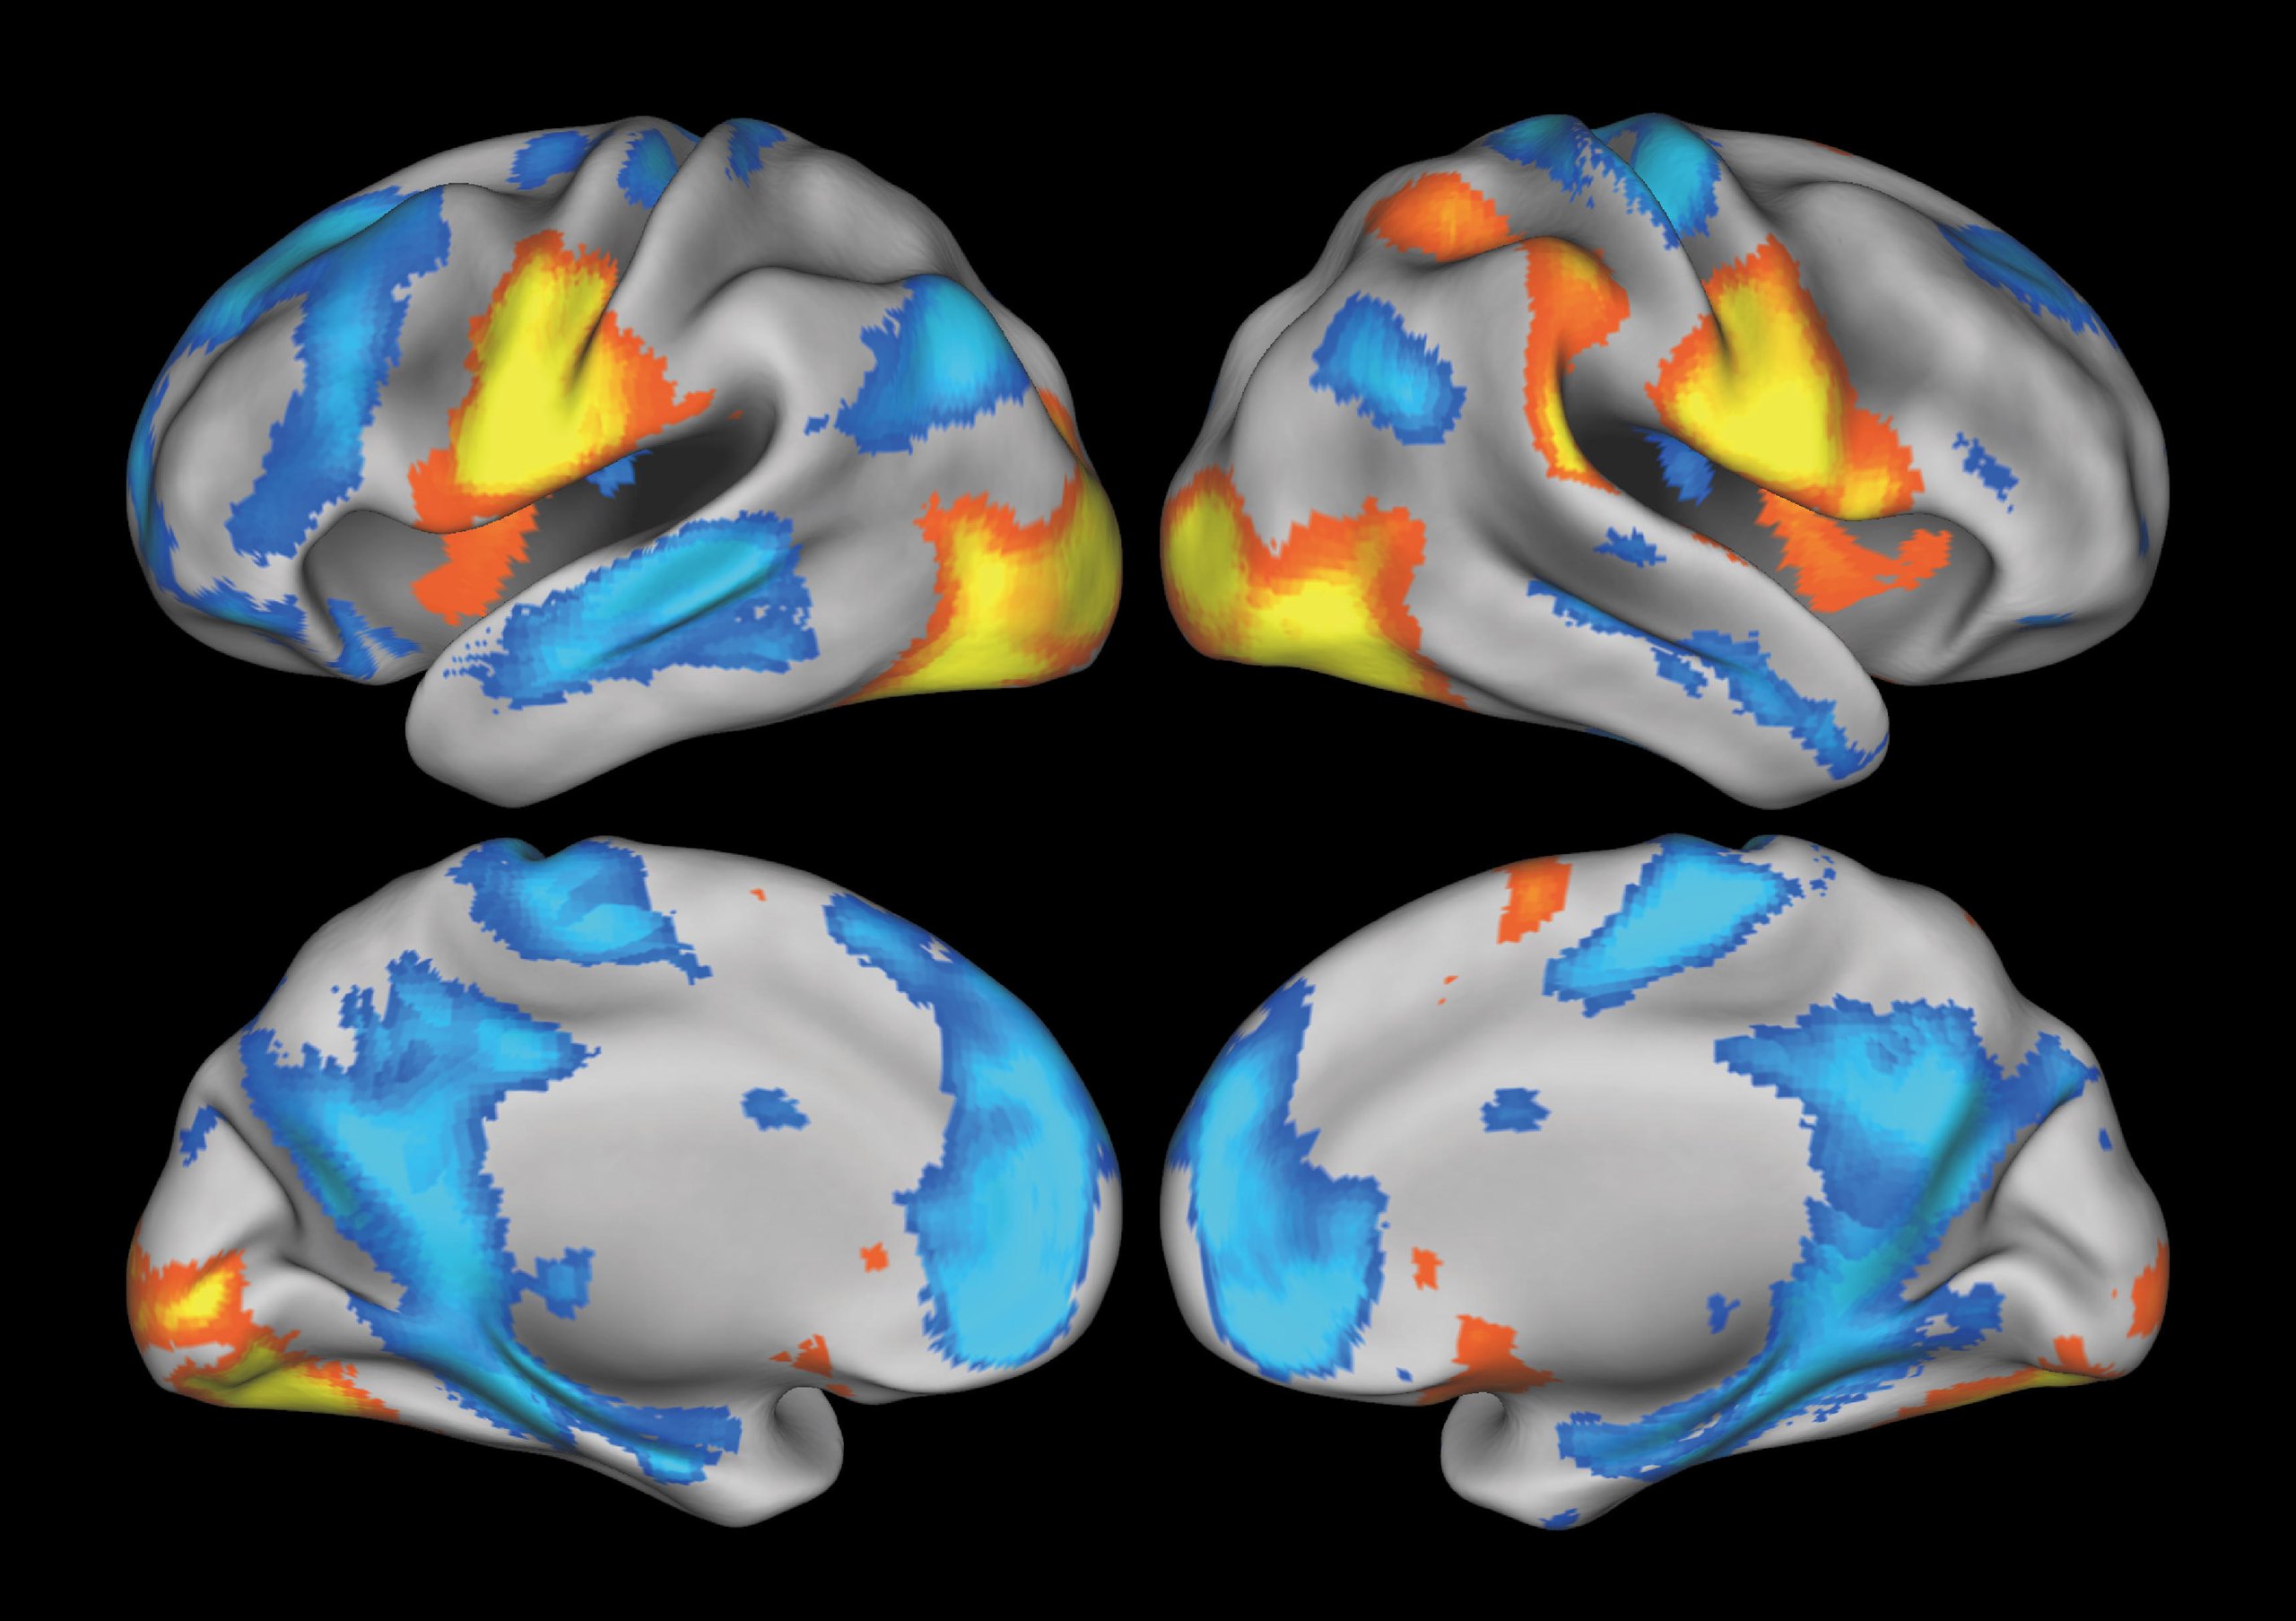

Functional MRI allows us to measure activity across all regions of the brain, one of the largest organs in the human body, without causing any damage (Figure 2). Using this method, we can investigate which areas of the brain are active, under what conditions, and in what way (Figure 3). This offers the potential to understand the workings of the mind as information processing in the brain. Importantly, this scientific framework solves the problems faced by the pioneers mentioned above by enabling an empirical understanding of the mind.